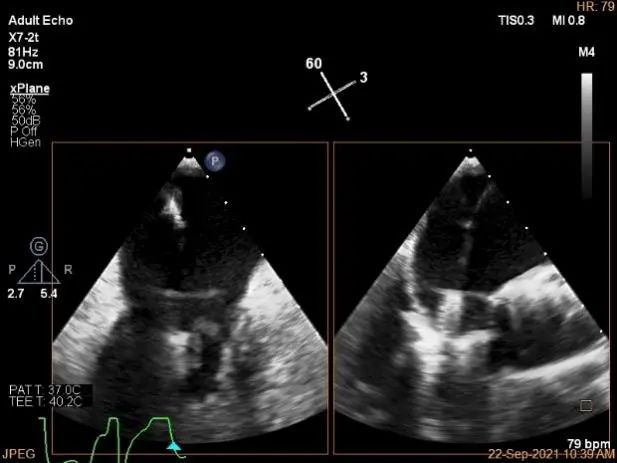

术中超声

P2区脱垂,宽14.8mm,Gap:3.3mm

3D-color,返流重度,3+级

麻醉状态下左肺静脉血流频谱

MVA:6.67cm²

房间隔穿刺点选择

穿刺高度:4.3cm